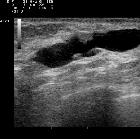

Breast ultrasound

Papilloma may be seen as a well-defined solid nodule or intraductal mass which may either fill a duct or be partially outlined by fluid - either within a duct or by forming a cyst. Color Doppler will demonstrate a vascular stalk.

A dilated duct can be frequently visible sonographically.